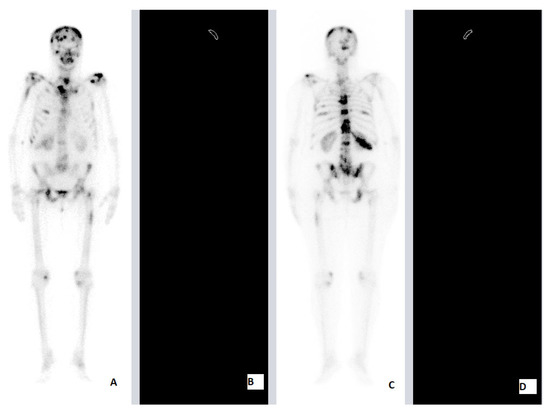

| BCa | 60 | F | HFRT | 20 Gy (4 Gy) | Brain LG 5th, 10th, 11th, 12th TV 1st, 2nd LV Rhs Ischium Pelvis Lhs Fmr Rhs Fmr 12th Rhs Rib Rhs Clc LNMs | 10th, 11th, 12th TV 1st, 2nd LV | SkC 12th Rhs Rib Rhs Clc Lhs Fmr | 2 | 8 | ||